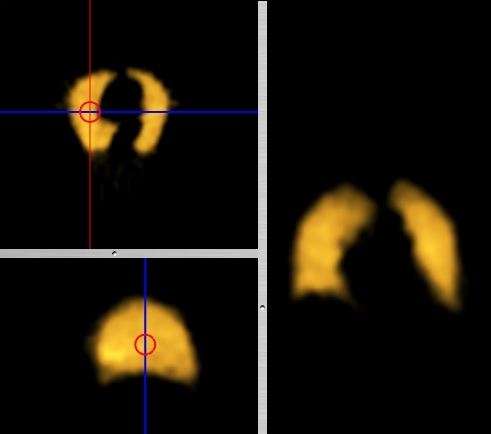

- Coronal and sagittal reconstructions are referred to as Orthogonal MPRs because the perspectives generated are from planes of image data which are at right angles to each other. Composite MPR displays can be generated so that linked cursors or crosshairs can be used to locate a point of interest from all three perspectives, as illustrated in these images:

|

|

- This form of image presentation is sometimes referred to as a TCS display - implying the viewing of Transaxial, Coronal and Sagittal slices. It can be combined with the slice projection methods we discussed earlier, as illustrated in the two sets of images below, where the blue lines highlight the limits of the coronal projections: